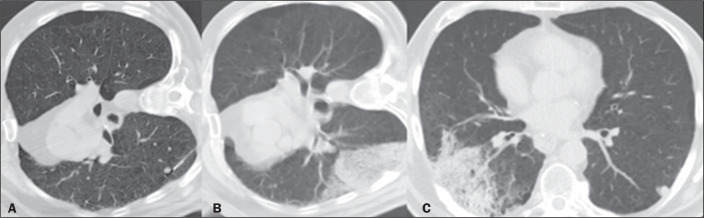

Objective: To assess the diagnostic success rate and complications of computed tomography (CT)-guided percutaneous biopsy in pulmonary nodules < 10 mm in diameter.

Materials and methods: This was a retrospective, single-center study involving the review of medical records, images, and chest CT reports related to 115 patients who underwent percutaneous CT-guided biopsy of < 10 mm pulmonary nodules between July 2015 and January 2019.

Results: Nodule diameter on the longest axis ranged from 4 mm to 9 mm, with a mean size of 7.7 mm. The mean age of the patients at the time of the procedure was 61 years, and 54.7% were women. Of the 115 nodules evaluated, 77 (67.0%) were solid and 55 (47.8%) were located in the lower lobes. The mean distance traversed by the needle in the lung parenchyma was 20 mm (range, 0-70 mm), and, in most cases, the biopsy was not performed with the patient in the biopsy-side-down lateral position. The diagnostic success rate was 93.0%. The most common complications were alveolar hemorrhage (in 36.5% of cases) and pneumothorax (in 24.3%).

Conclusion: The data suggest that CT-guided percutaneous biopsy of < 10 mm pulmonary nodules has a high diagnostic success rate and an acceptable rate of complications.